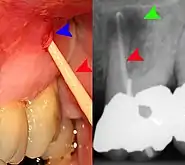

Apical periodontitis is acute or chronic inflammation around the apex of a tooth caused by an immune response to bacteria within an infected pulp.[20] It does not occur because of pulp necrosis, meaning that a tooth that tests as if it's alive (vital) may cause apical periodontitis, and a pulp which has become non-vital due to a sterile, non-infectious processes (such as trauma) may not cause any apical periodontitis.[10]:225 Bacterial cytotoxins reach the region around the roots of the tooth via the apical foramina and lateral canals, causing vasodilation, sensitization of nerves, osteolysis (bone resorption) and potentially abscess or cyst formation.[10]:228

The periodontal ligament becomes inflamed and there may be pain when biting or tapping on the tooth. On an X-ray, bone resporption appears as a radiolucent area around the end of the root, although this does not manifest immediately.[10]:228 Acute apical periodontitis is characterized by well-localized, spontaneous, persistent, moderate to severe pain.[6]:125–135 The alveolar process may be tender to palpation over the roots. The tooth may be raised in the socket and feel more prominent than the adjacent teeth.[6]:125–135

- Radiographs utilized to find dental caries and bone loss laterally or at the apex.

Decay (green) with apical abscess (blue)

Gutta-percha point indicating abscess origin